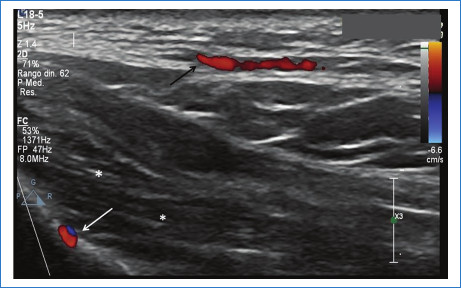

Del grupo 1 (n = 53, 63% del total de pacientes), 51 (96,2%) pacientes eran de sexo femenino y 2 (3,7%) de sexo masculino, 24 (45,2%) no presentaban rellenos previos, 15 (28,3%) presentaban ácido hialurónico (AH) y 14 (26,4%) tenían rellenos permanentes (biopolímeros, silicona y polimetilmetacrilato). Además, 12 (22,6%) pacientes de este grupo presentaron variantes anatómicas, de los cuales solo uno tenía un relleno previo de AH. Entre las variantes encontradas se mencionan arterias angulares, labiales, nasal dorsal y temporal profunda en sitios habituales de inyección de rellenos, glándulas parótidas prominentes y venas intercantales prominentes en sitios de inyección frecuentemente utilizados (Figs. 1, 2 y 3). En este grupo se presentaron 2 (3,7%) pacientes con prótesis faciales. Del total de pacientes que integraron este grupo, el informe ecográfico modificó la conducta del médico estético en el 60% (32) de ellos.

Con respecto a la topografía de las arterias labiales superior e inferior, se ha publicado que generalmente se encuentran en el plano submucoso (58,5%), seguido del plano intramuscular (36,2%) y menos frecuentemente subcutáneo (5,3%)9,10. En este sentido, un sitio habitualmente utilizado de inyección es el plano superficial subcutáneo para evitar un compromiso vascular.

En nuestro trabajo encontramos cinco pacientes con arterias subcutáneas (superficiales), hallazgo que condicionó un cambio en la conducta del médico inyector, si bien se mantuvo el plano superficial del relleno, se inyectó menor cantidad y más lento para reducir el riesgo de compromiso vascular.

La inyección de material de relleno en la región nasal, ampliamente conocida como “rinomodelación sin cirugía”, es uno de los procedimientos más riesgosos, ya que una inyección accidental intravascular de la arteria nasal dorsal podría condicionar compromiso de la arteria oftálmica con riesgo de ceguera permanente12. La técnica de inyección de rellenos mayormente utilizada es en el plano supraperióstico y siguiendo la línea media para evitar el compromiso de las arterias nasales dorsales8,13. En nuestro estudio, encontramos a un paciente que presentaba una variante anatómica de las arterias dorsales nasales, con doble arteria nasal dorsal izquierda, y otro paciente con venas intercantales prominentes y supraperiósticas; estas variantes incrementan el riesgo de eventos vasculares no deseados14.